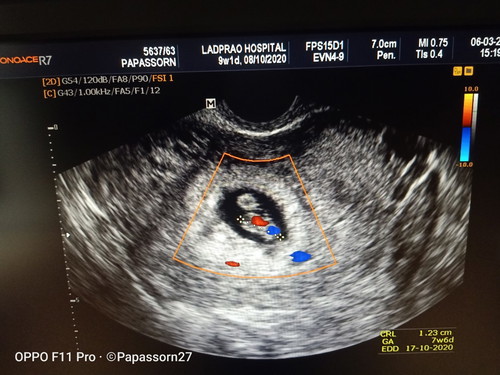

นับอายุครรภ์ ประจำเดือน9w1d เครื่องซาวด์7w6d ยึดตามอันไหนคะ